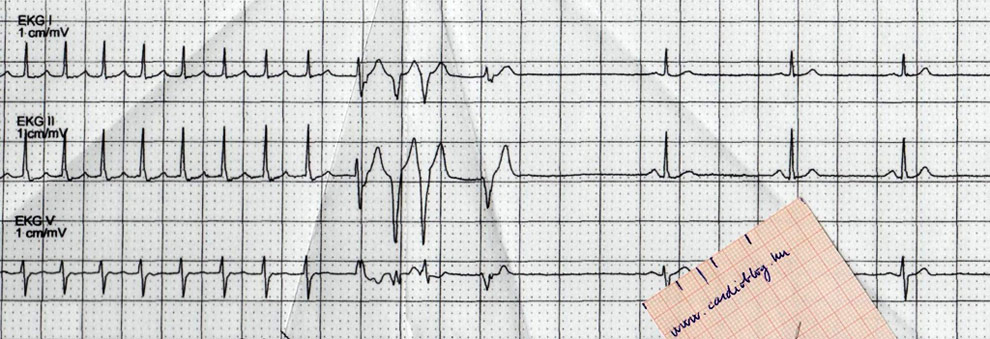

A beteg nyugalmi EKG-ján eltérés nem ábrázolódott. A terheléses EKG vizsgálat során a beteg mellkasi fájdalmat jelzett, V4-V6 szignifikáns STD, T-inverzió alakult ki.